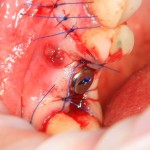

Немедленная имплантация — оптимальное решение в любой клинической ситуации